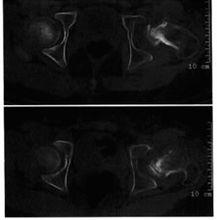

左股骨頭骨骺缺血性壞死(進展期)圖9-5左股骨頭骨骺缺血性壞死(進展期)

CT平掃,示左髖股骨頭骨骺變扁.密度增高,關節面不平整,間隙增寬